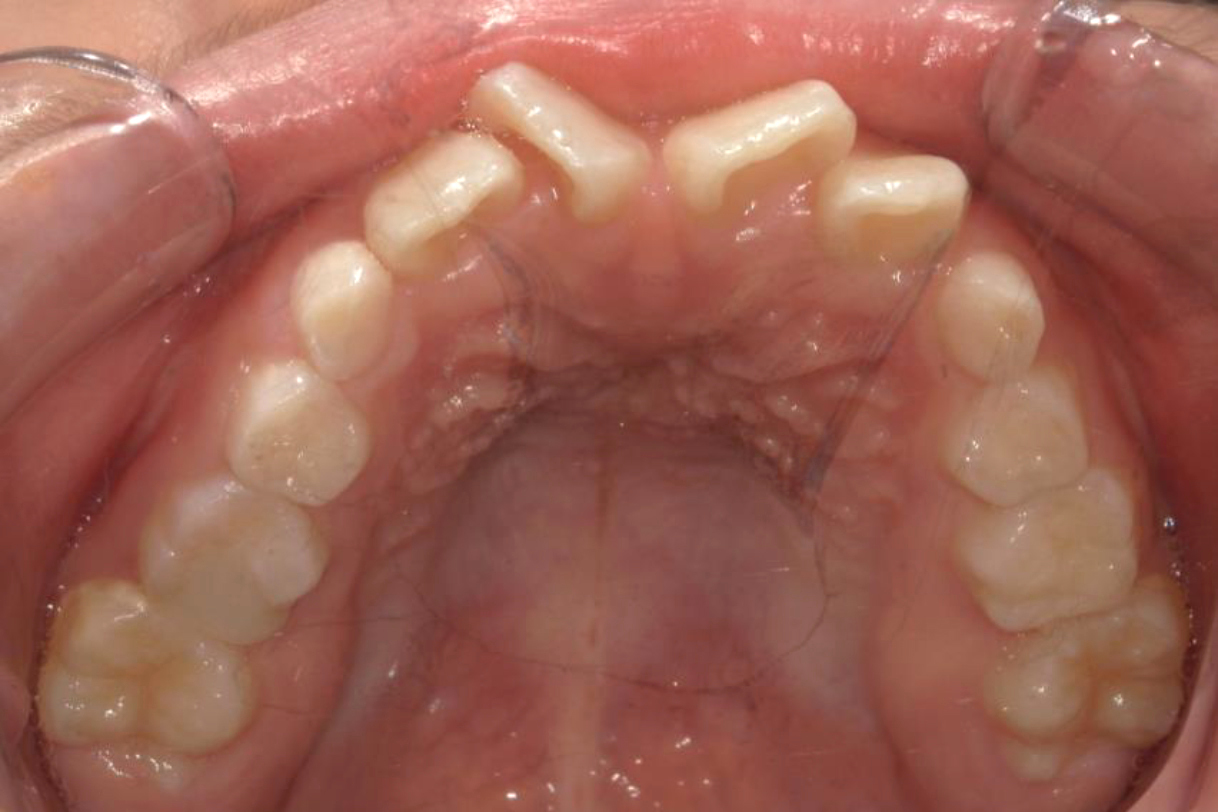

初診時年齢:7歳

治療:前歯部矯正

治療法:上顎前歯部表側の装置

治療期間:2ヶ月

費用:110,000円(税込)

リスク・副作用:装置装着による違和感、歯の移動時の痛み